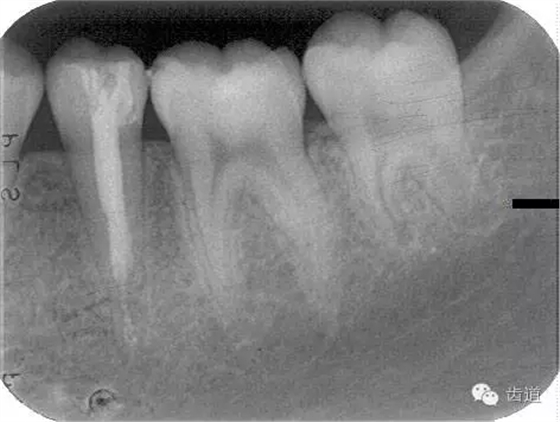

牙根發(fā)育情況-open apex

內(nèi)吸收 inner resorption

根管鈣化 calcified masses in canal

根尖周組織 periapical tissue

3個(gè)月左右在X線片上可觀察到修復(fù)性牙本質(zhì)層的出現(xiàn), 術(shù)后6個(gè)月左右,常可觀察到連續(xù)的有一定厚度的修復(fù)性牙本質(zhì)層; 修復(fù)性牙本質(zhì)層的出現(xiàn),是間接牙髓治療成功的重要指征。

1.術(shù)前X線片

術(shù)前

術(shù)后199日

術(shù)后1084日